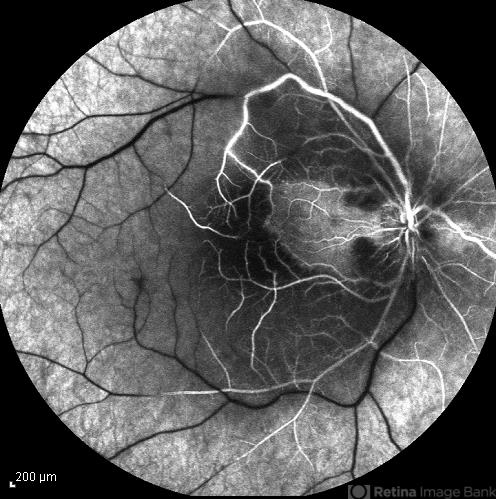

- central retinal artery occlusion (CRAO), cilioretinal sparing

- FA image of the right eye of a 34-year-old man with sudden drop of vision due to CRAO. The macula is involved despite cilioretinal artery sparing .